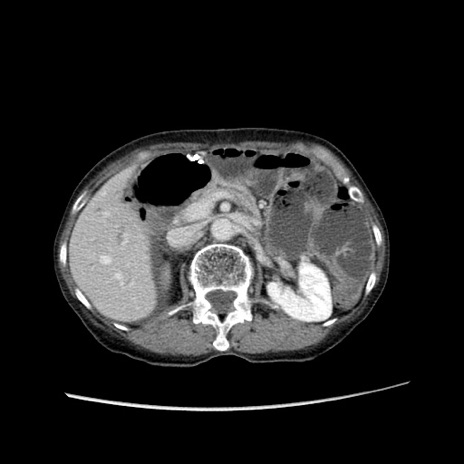

症例25(横断像)

【症例】80歳代女性

【主訴】胸のつかえ感

【現病歴】約9時間前に食後から胸のつかえた感じあり、嘔吐あり、来院。

【既往歴】胃癌(全摘)、胆摘、虫垂炎

【身体所見】心窩部に圧痛あり、反跳痛なし。

【データ】WBC 5700、CRP 0.05